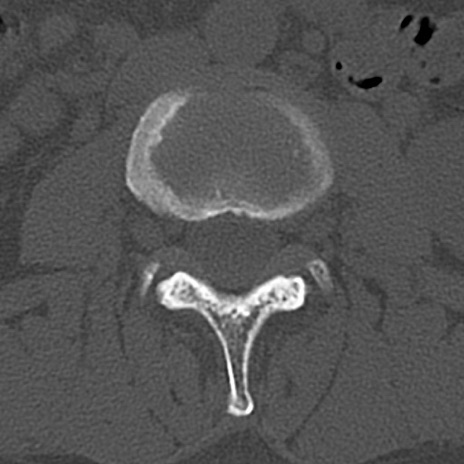

腰椎CT

横断像と矢状断像